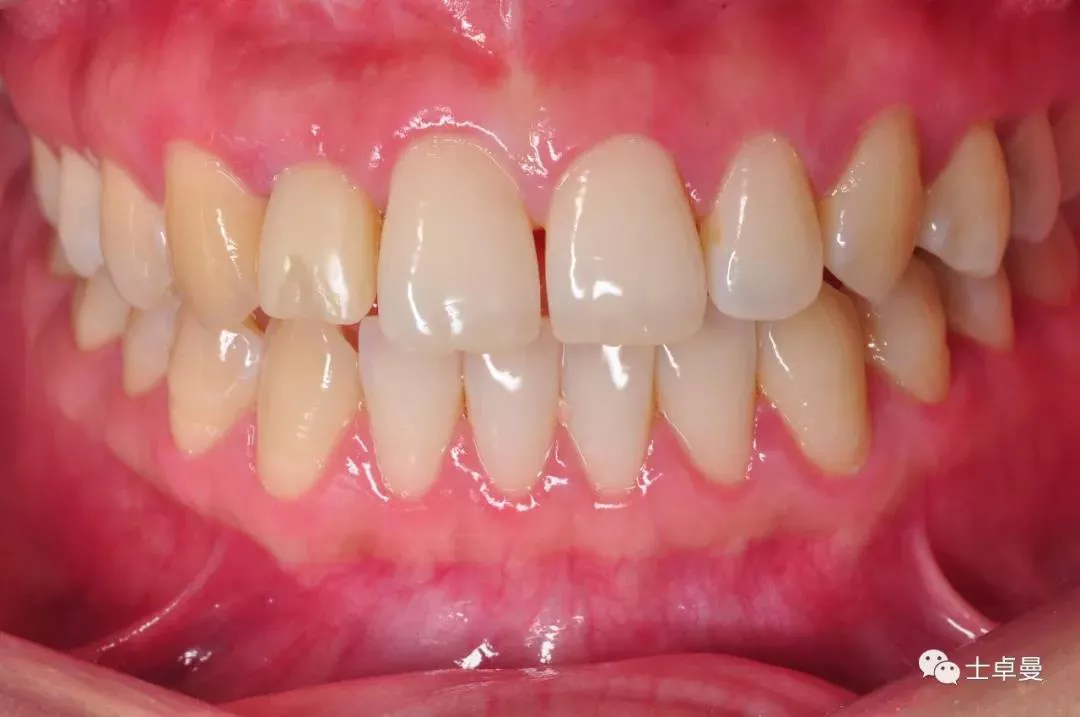

口内完成修复当日

完成修复一年后复查

修复后3年复查

患者微笑照